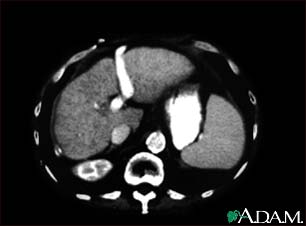

A CT scan of the upper abdomen showing cirrhosis of the liver.